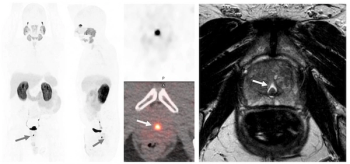

Sixty-five percent of patients with newly diagnosed high-risk prostate cancer may have extraprostatic extension on MRI, and PSMA PET/CT findings suggest those with Gleason scores of eight or higher have more than double the risk of metastasis, according to a new study presented at the European Congress of Radiology (ECR).